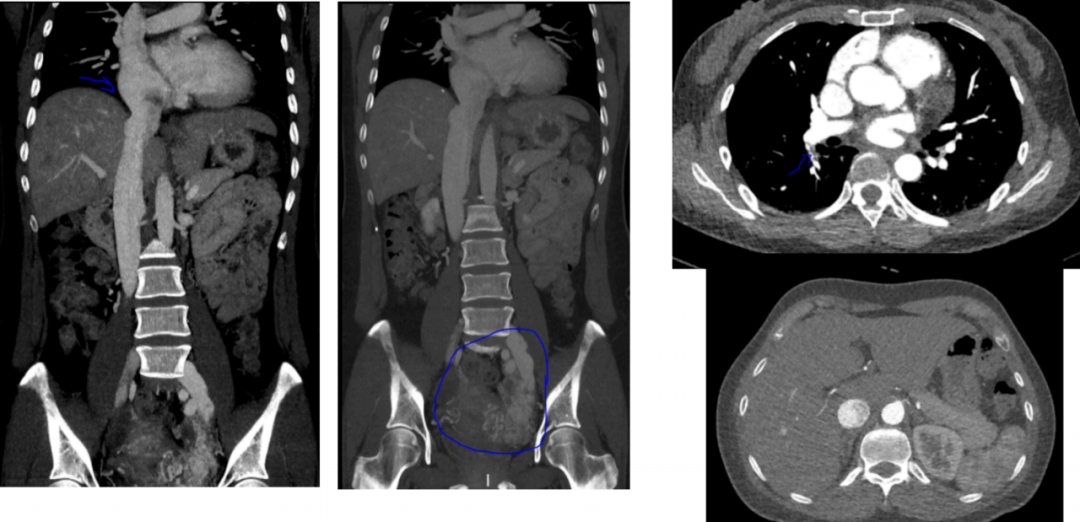

治疗团队首先安排患者进行了三维超声心动图 CT 全主动脉造影,结果显示,患者右心增大,右心房内有稍高回声团,这表明患者可能存在心房肿瘤或心房血栓。

与此同时,全主动脉造影还发现,患者的病变并不止心脏,其盆腔左侧存在多发的增粗迂曲血管影,意味着可能是动静脉畸形。

考虑到患者为女性,45 岁正是围绝经期,并且患者表示自己近 2 月有月经不规律的情况,因此又补充了妇科影像学检查。其中的盆腔增强 CT 显示,患者子宫多发肌瘤,右侧附件区囊肿,盆腔左侧血管曲张,左髂静脉、下腔静脉可疑充盈缺损。

盆腔增强 CT

围绝经期女性、子宫肌瘤、血管异常、心脏肿瘤,这几个关键词一结合,治疗团队很快想到了一种临床表现缺乏特异性的少见良性疾病:静脉内平滑肌瘤病(intravenous leiomyomatosis,IVL)。

下肢静脉 CTA

本例患者就是一例肿瘤从盆腔一路「长」到心脏的案例。「虽然影像学上无法准确测量肿瘤的总长,但可以参考从胸骨柄到肚脐的距离。保守估计全长应该超过了 30 公分。」